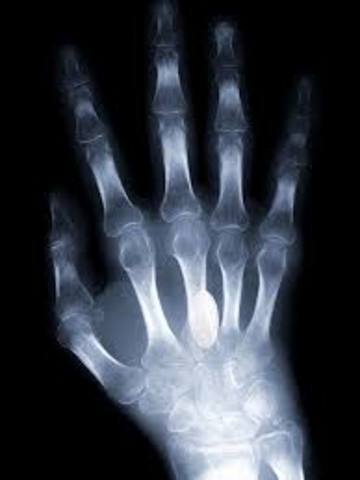

Discovery

Organ transplants, X-rays, radium for cancer treatment, MRI, and CAT scans are discovered.